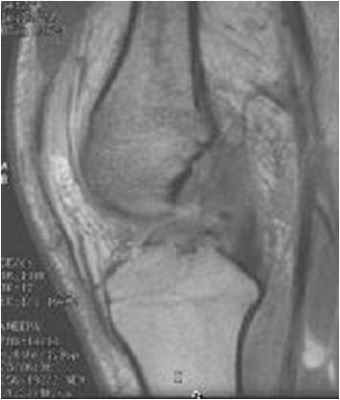

МРТ коленного сустава. Т1-взвешенная сагиттальная МРТ. Крестообразные связки в норме.

Крестообразные связки расположены внутри сустава. При МРТ коленного сустава можно проследить, что ПКС начинается от задне-медиального края латерального мыщелка бедренной кости и прикрепляется к большеберцовой кости кзади от её переднего края, сразу кпереди и латеральнее медиального межмыщелкого выступа. Длина ПКС около 3,5 см, диаметр около 1 см.

ЗКС, как видно при МРТ коленного сустава, начинается от латеральной поверхности медиального мыщелка бедренной кости и крепится к суставной поверхности плато большеберцовой кости. Как и ПКС, она расположена внутри сустава, но вне синовиальной оболочки. Связка в 2 раза мощнее ПКС и тесно связана с мениско-феморальными связками (Ризберга и Хамфри)